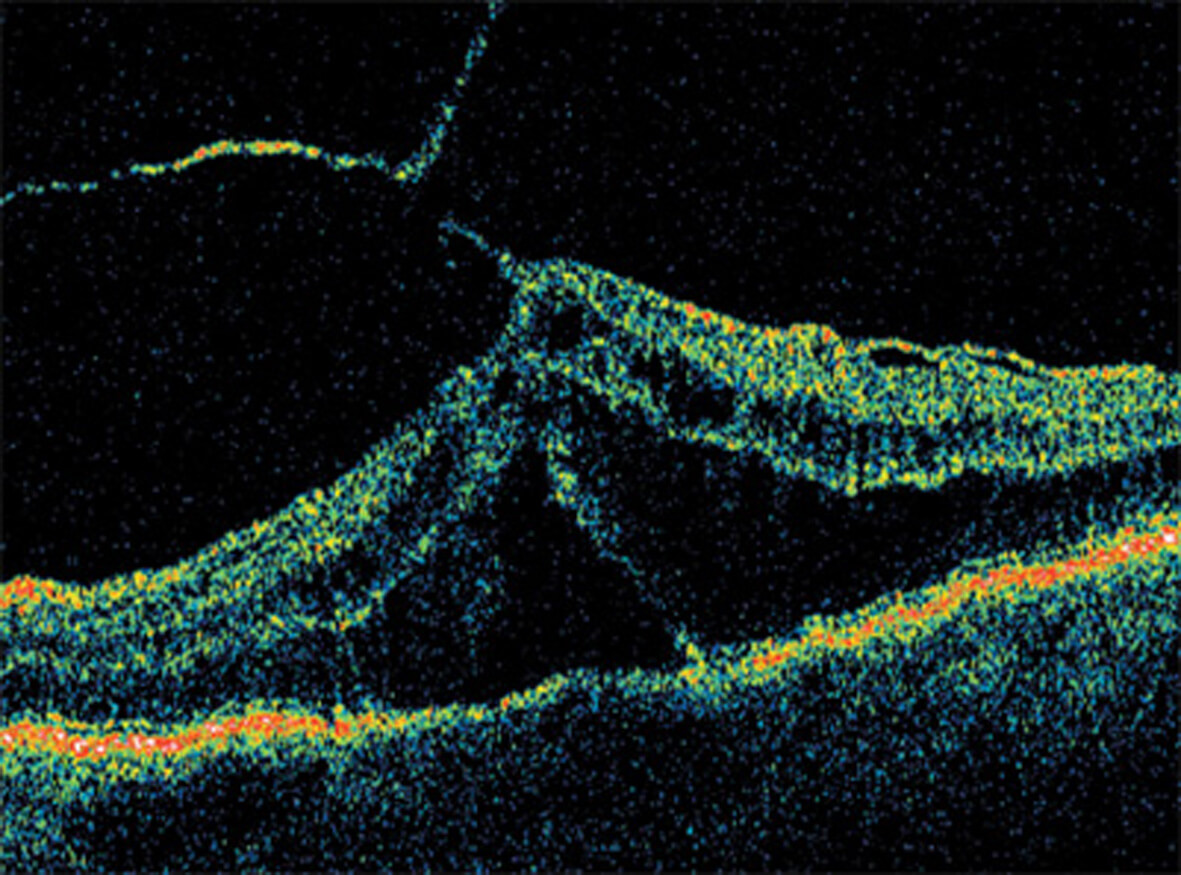

Optical Coherence Tomography (OCT) is an advanced eye scan, similar to ultrasound. The OCT uses light rather than sound waves to illustrate the different layers that make up the back of the eye. Within 2 seconds, the OCT takes over 30,000 individual scans of the back of the eye and this is used to produce a 3D image of the retina and optic nerve. The scan gives an accurate cross-sectional map through the retina and allows examination of the back of the eye in incredibly fine detail.

The OCT also captures a digital photograph of the surface of the eye at the same time, and this can then be cross-referenced with any areas of concern.

The scan shows us beneath the surface of your retina, so we can see and better understand the very fine changes which can be indications of something unhealthy or abnormal.